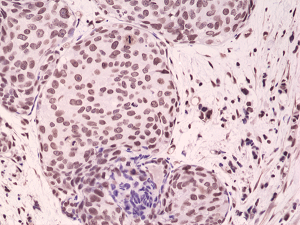

Recombinant Antibody. This antibody reacts to p38 MAPK only when dual phosphorylation at Thr180 and Tyr182 is observed. There is no cross-reactivity with p38 MAPK without dual phosphorylation at Thr180 and Tyr182. Applications: WB, IHC. Source: Rabbit. Liquid. 50% Glycerol/PBS with 1% BSA and 0.09% sodium azide. p38 MAP kinase (MAPK) participates in a signaling cascade controlling cellular responses to cytokines and stress. Four isoforms of p38 MAPK, p38alpha, beta, gamma (also known as Erk6 or SAPK3), and delta (also known as SAPK4) have been identified. p38 MAPK is activated by a variety of cellular stresses including osmotic shock, inflammatory cytokines, lipopolysaccharide (LPS), UV light and growth factors. MKK3, MKK6, and SEK activate p38 MAPK by phosphorylation at Thr180 and Tyr182. Activated p38 MAPK has been shown to phosphorylate and activate MAPKAP kinase 2 and to phosphorylate the transcription factors ATF-2, Max and MEF2. MAP kinases act as an integration point for multiple biochemical signals, and are involved in a wide variety of cellular processes such as proliferation, differentiation, transcription regulation, and development.

| Application: | WB, IHC |